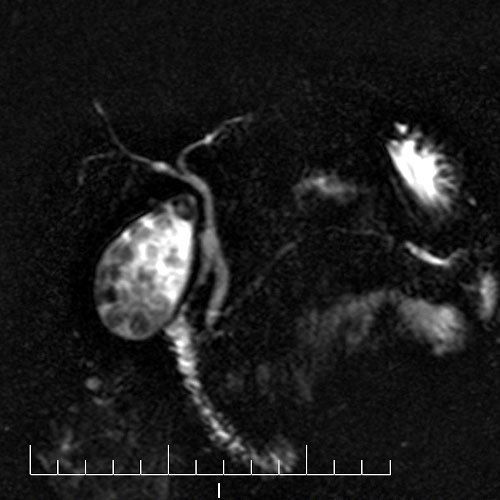

28 year old female with left lower abdomen pain. MRI showing torsion of Fallopian tube.